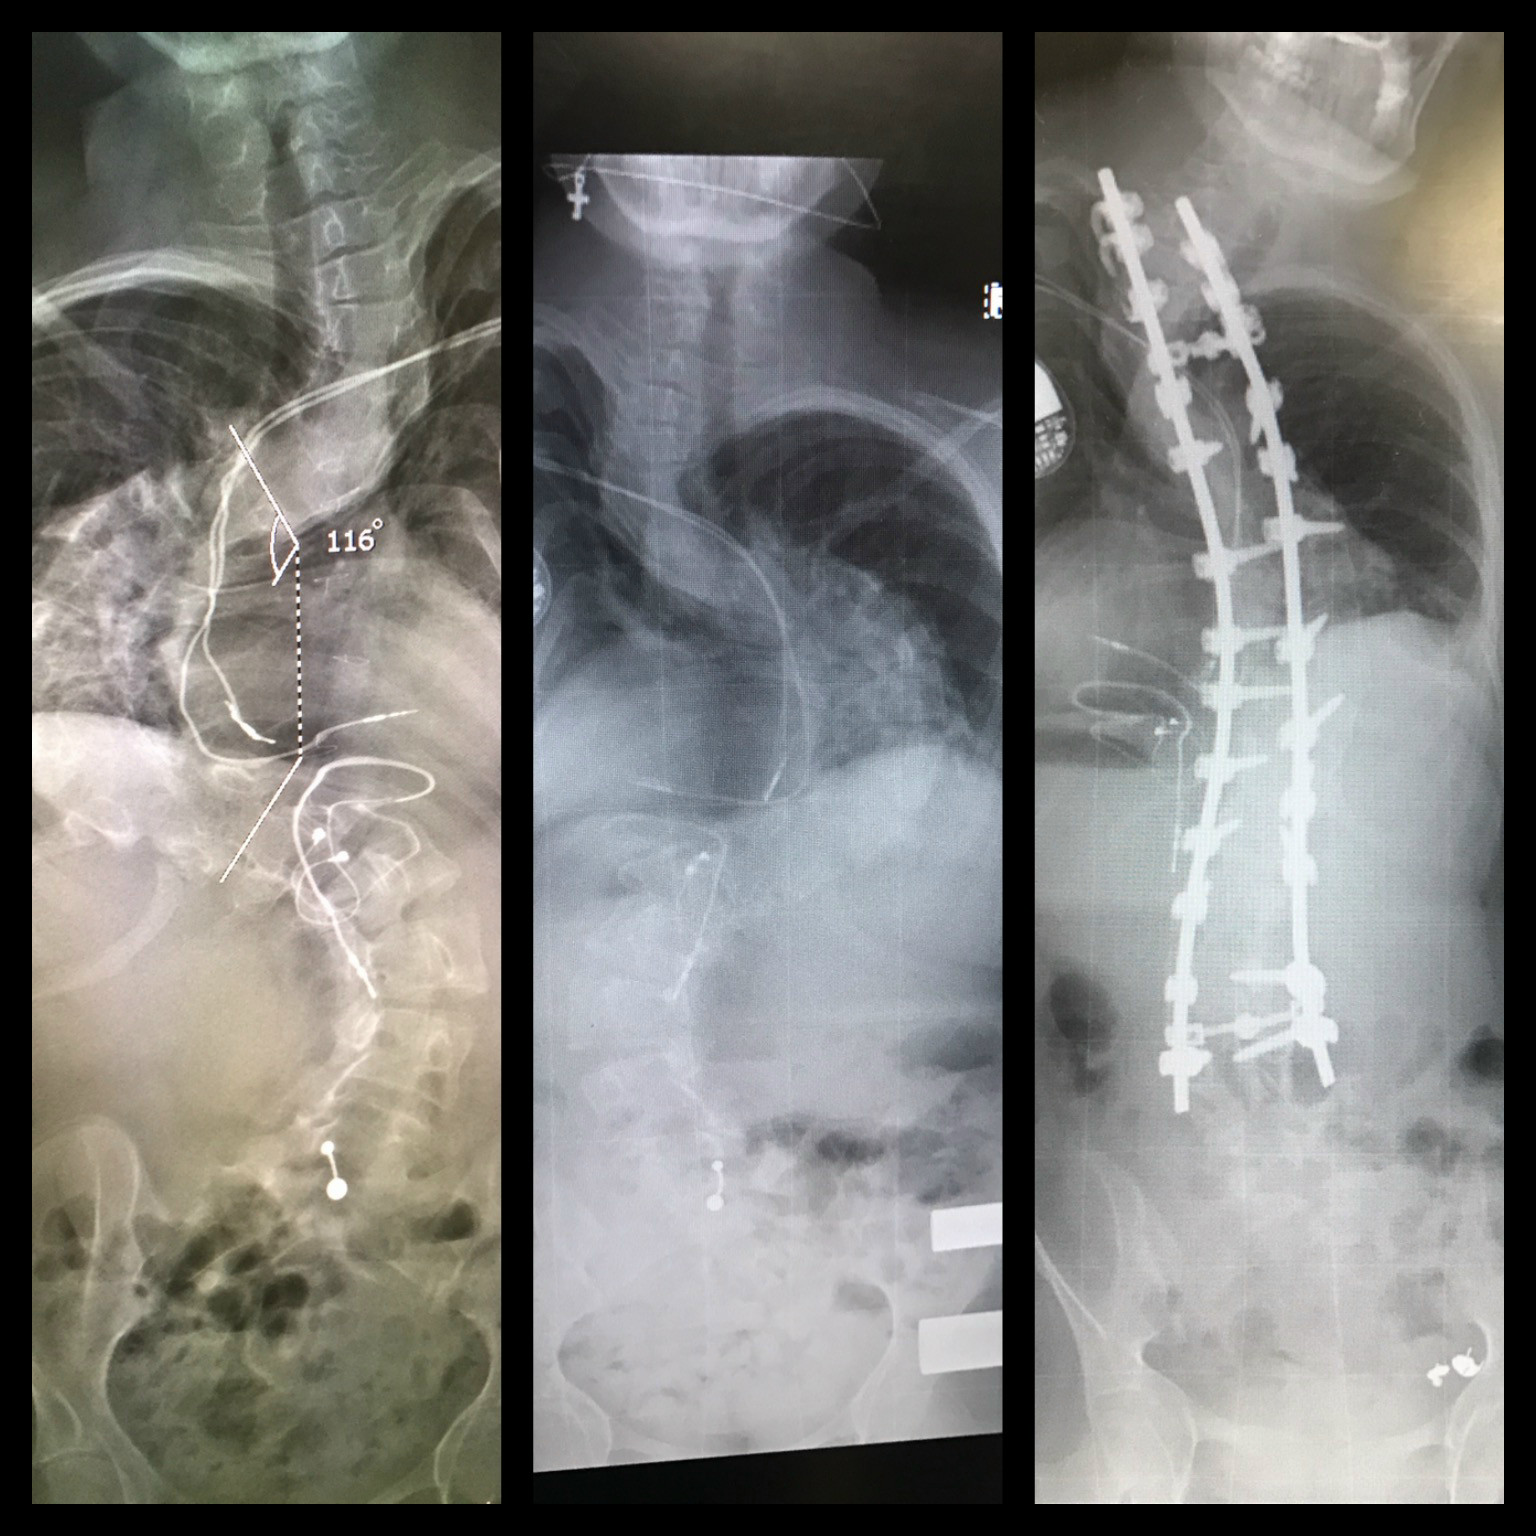

My name is Samantha Harris. I am nineteen years old and from Australia. I have scoliosis; one of the worse cases my surgeon has ever treated. Pre-operation my curve was sitting at a whopping 130 degrees!

I spent four and a half months in Halo gravity traction, which involved having a medical halo on and having it conected to 44lbs (20kgs) of weight! 24/7! And then I had a 12 hour surgery where they fused my spine, took a rib out, removed a veterbrae, and put rods and screws in. My spine now sits at 43 degrees!